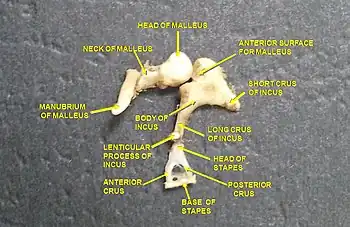

Ossicles

Ossicles Head and neck of a human embryo eighteen weeks old, with Meckel's cartilage and hyoid bone exposed.

CT image of malleus Auditory ossicles. Tympanic cavity. Deep dissection.

Auditory ossicles. Tympanic cavity. Deep dissection. Auditory ossicles. Incus and malleus. Deep dissection.

Auditory ossicles. Incus and malleus. Deep dissection.